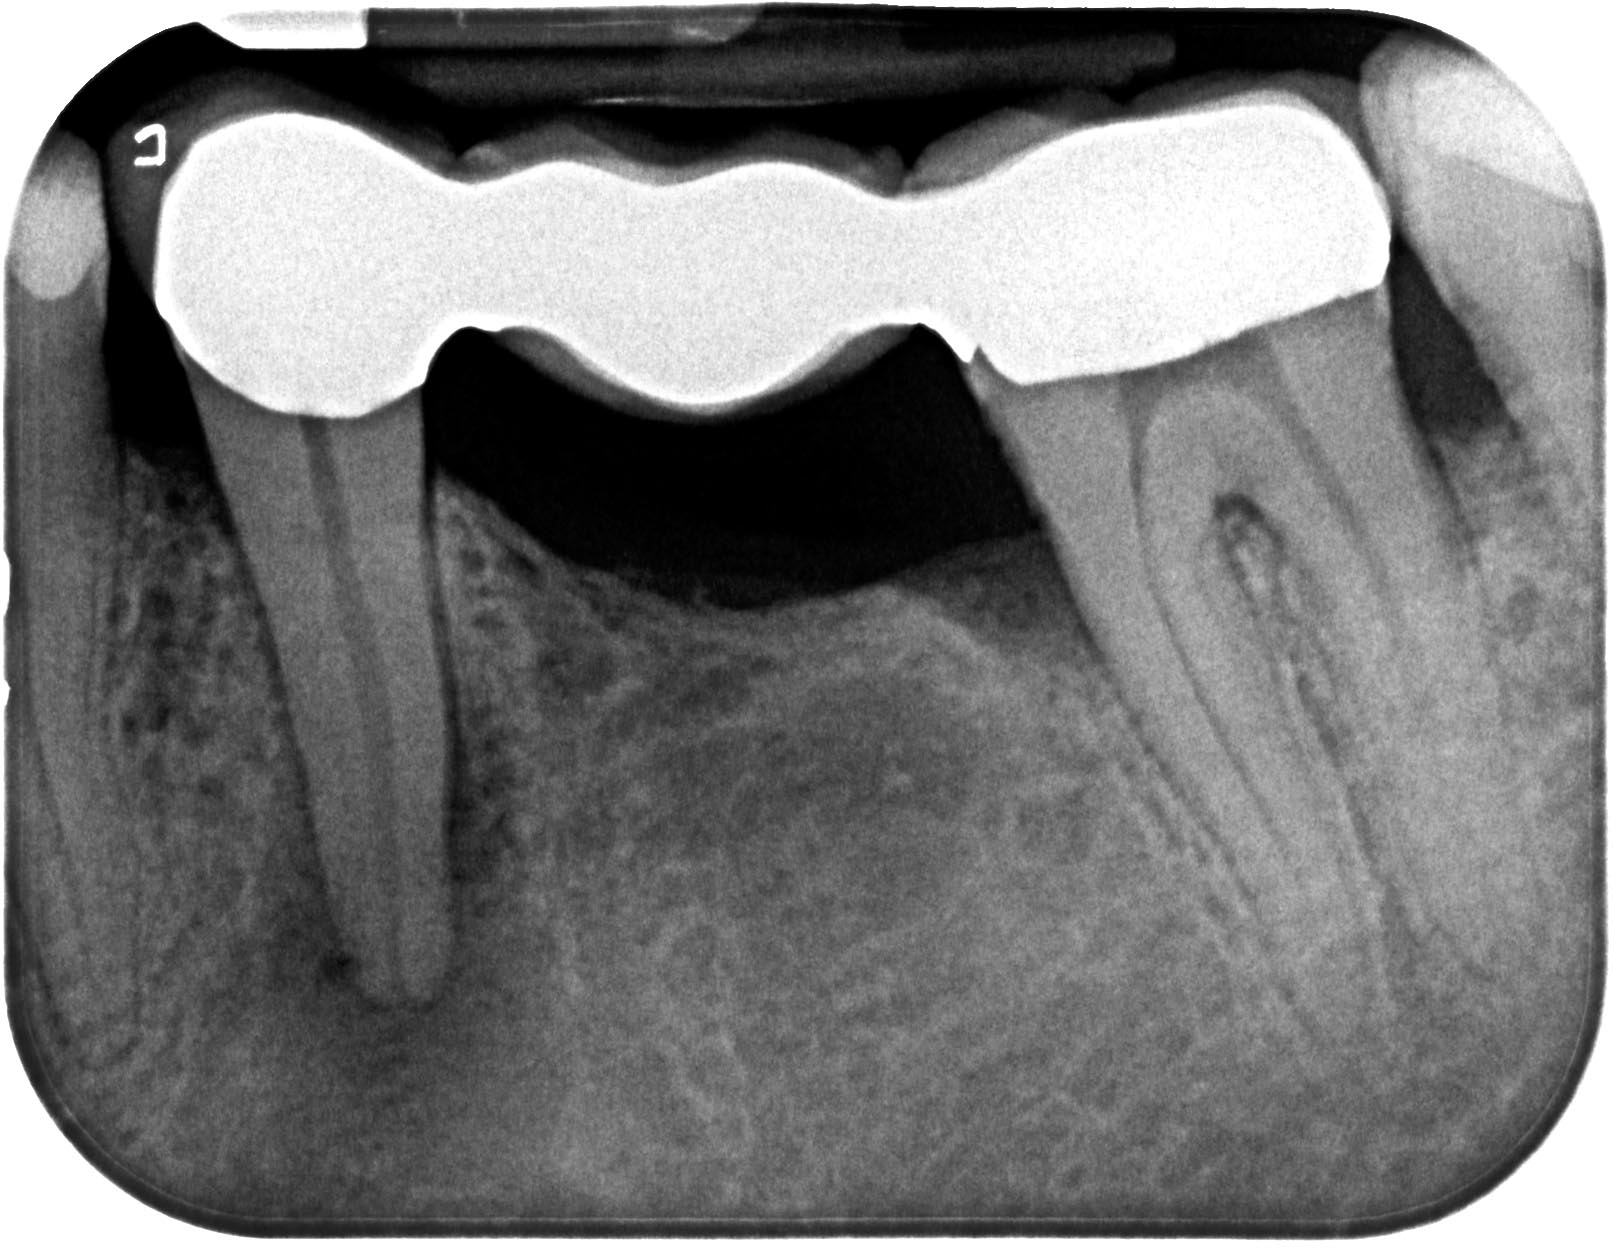

35 apikale Aufhellung 2011 Veröffentlicht 5. November 2013 am 1613 × 1247 in „Chapeau“ oder der Wirt und die Wette 35 apikale Aufhellung 2011